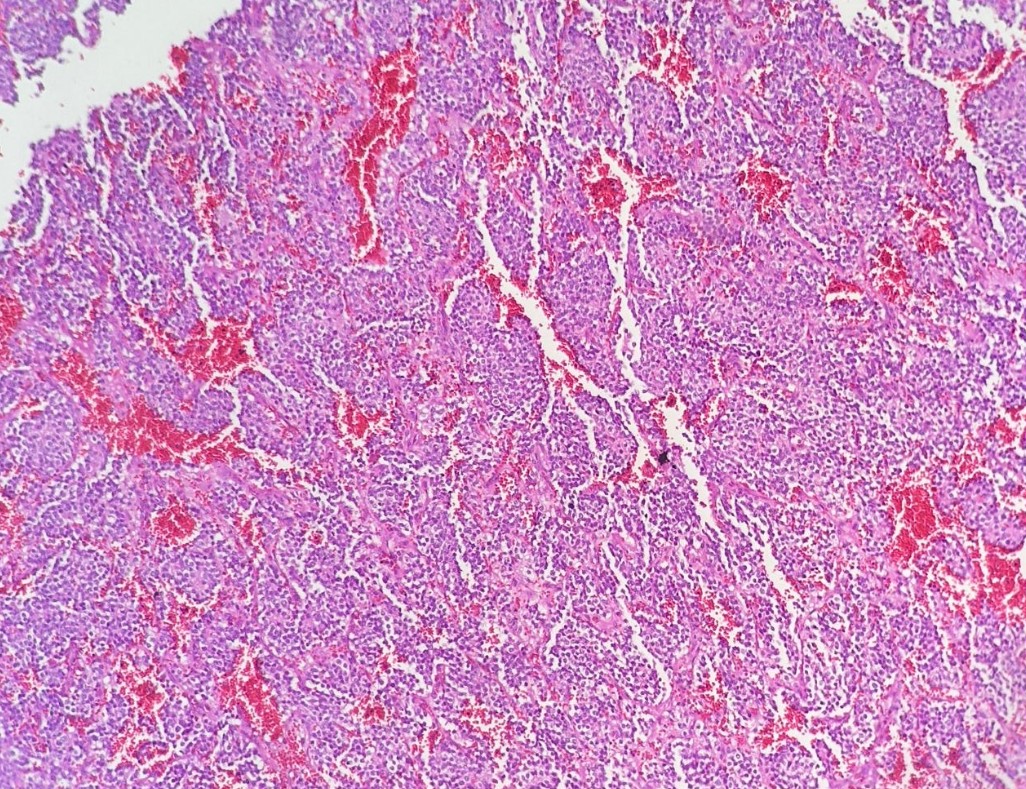

1. Con base a estas imágenes, cual sería tu diagnostico?

a) TUMOR GERMINAL MIXTO

b) RABDOMIOSARCOMA CON ANAPLASIA DIFUSA

c) NEUROBLASTOMA ANAPLASICO

d) TUMOR DE WILMS CON ANAPLASIA DIFUSA